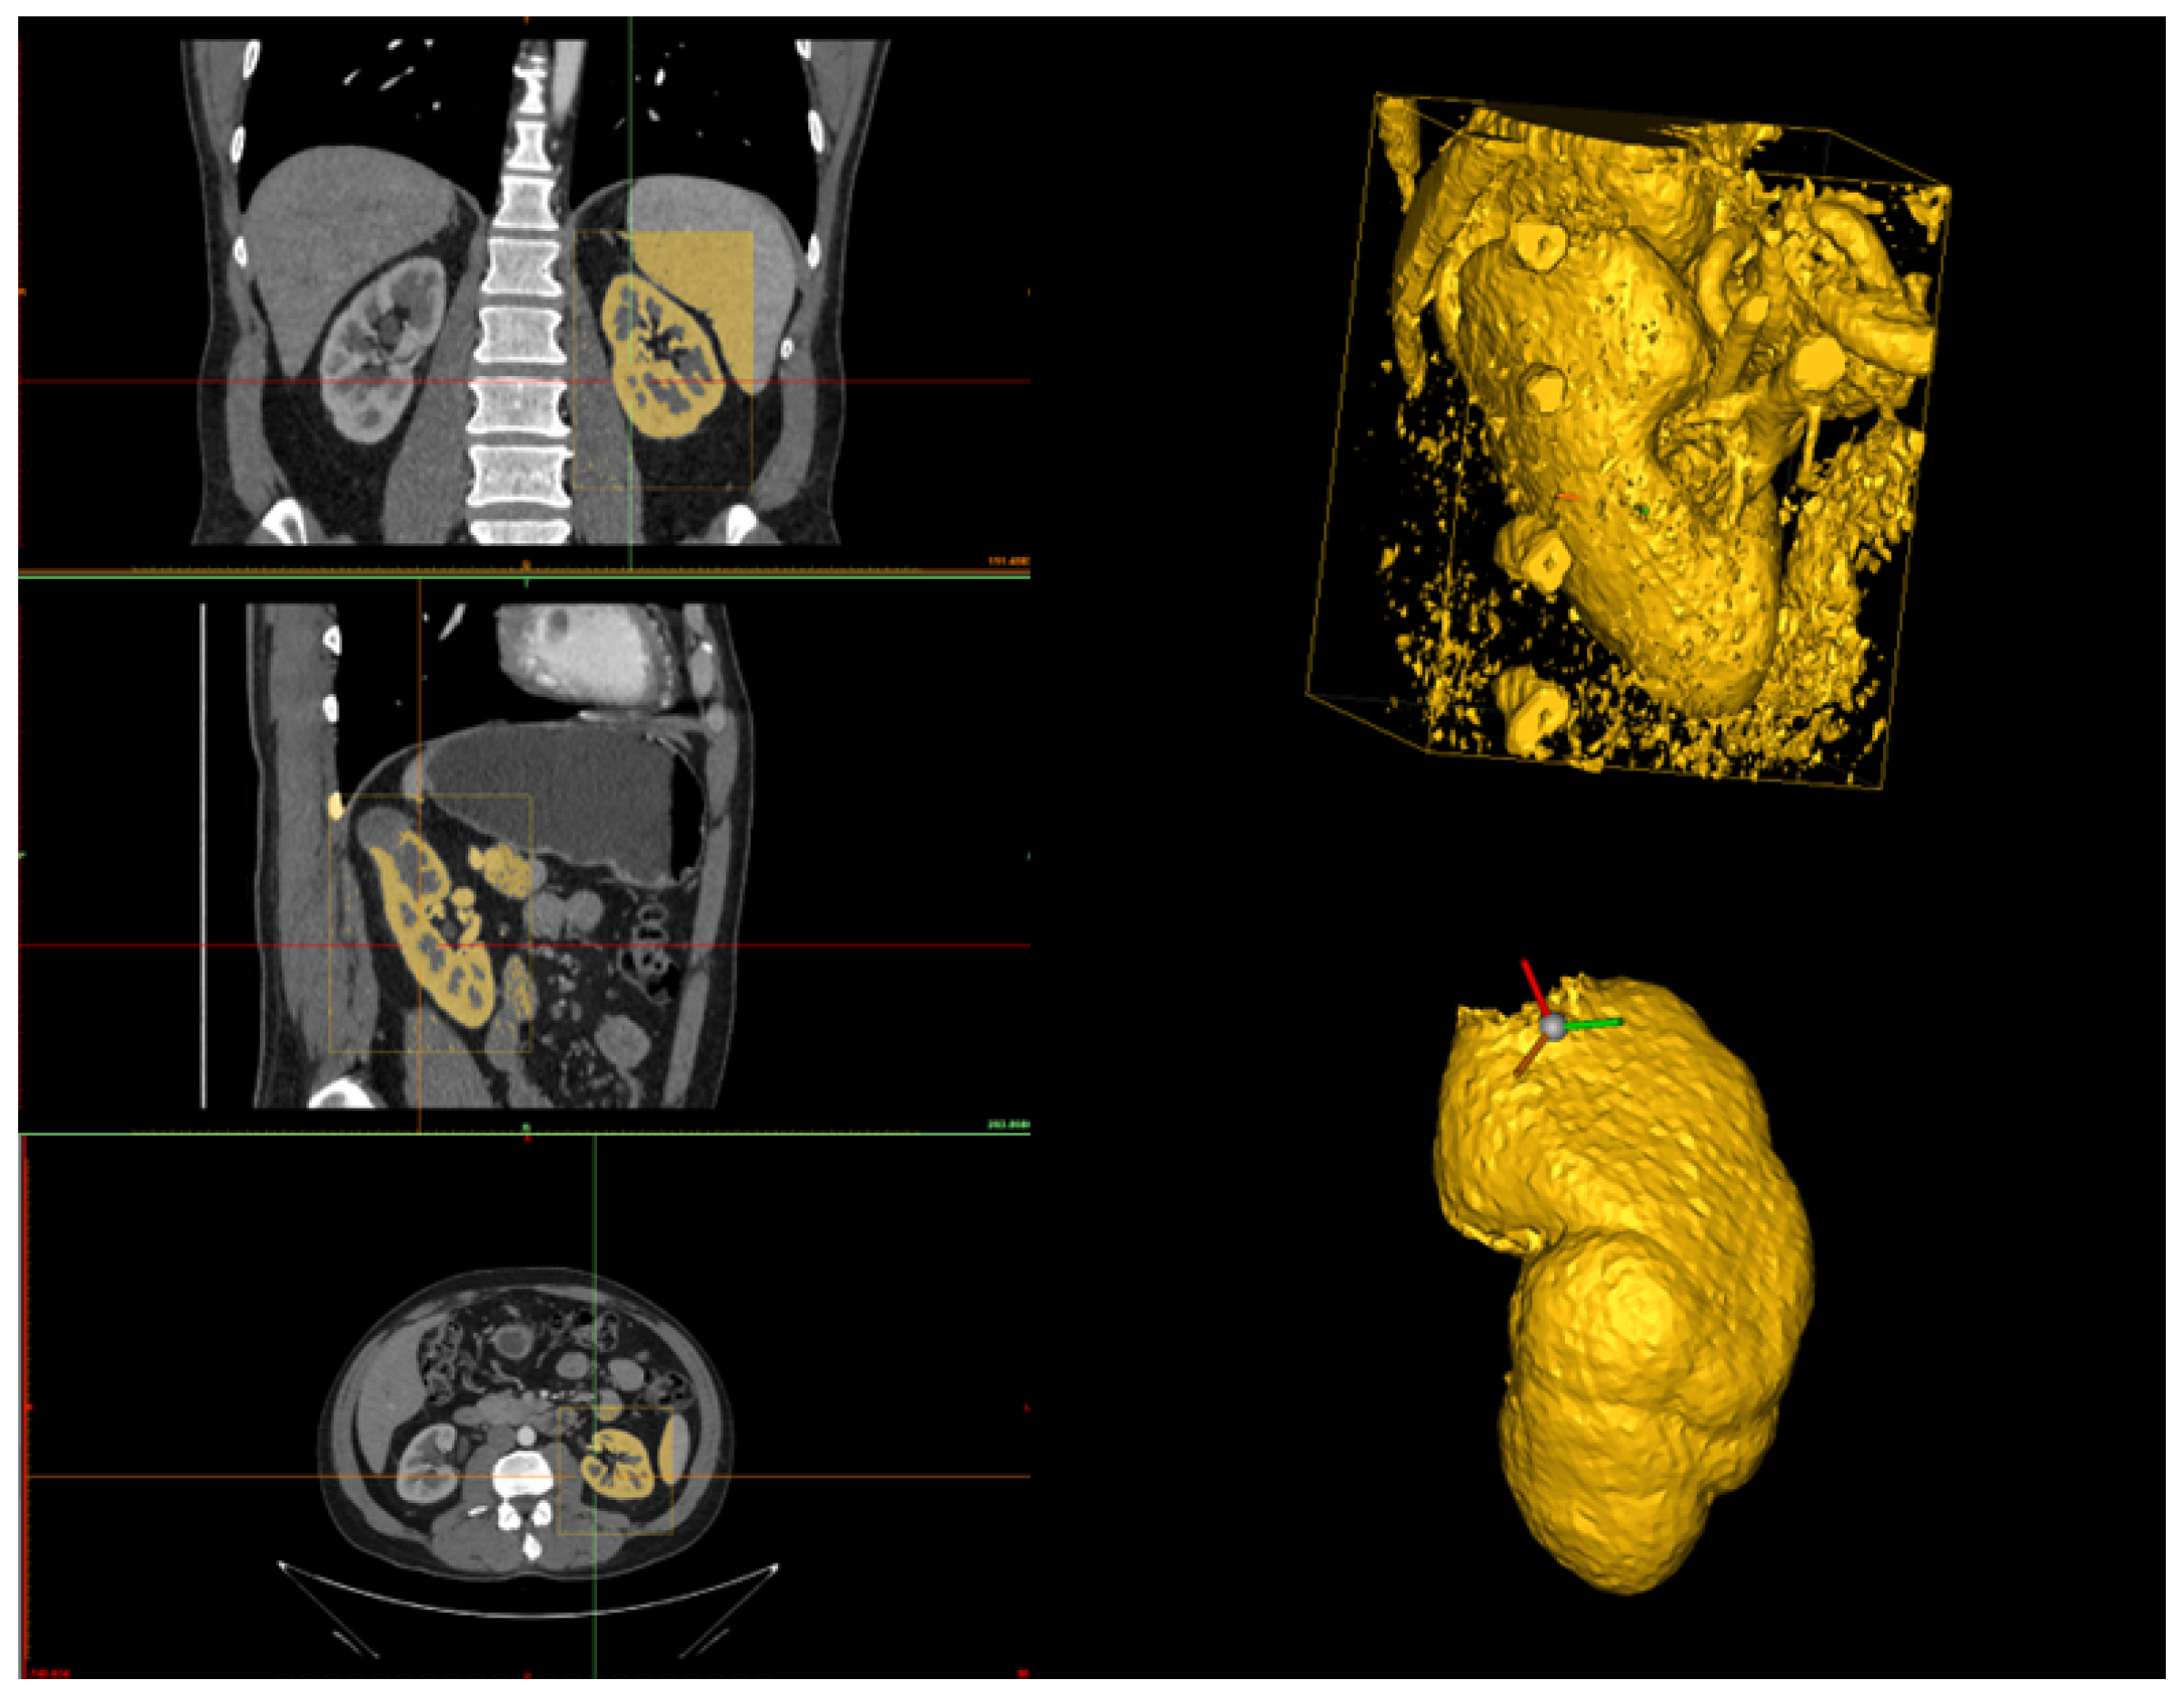

In this Section, we outline the segmentation protocol for obtaining accurate 3D reconstructions of organs and tumors. Our protocol is specific for the reconstruction of kidneys and their associated tumors. The main objective of the protocol is to describe how a human operator should proceed to segment the kidney and the tumor to ensure an accurate reconstruction. Therefore, we structured the protocol into three steps: kidney segmentation, tumor segmentation, and reconstruction refinement. After completing these steps, accurate 3D reconstructions were generated (see Figure 1) and exported as STL files. These files were then provided as input to our algorithm for calculating the CSA.

Therefore, the first step in correcting the reconstruction is to remove any tumor parts mistakenly considered part of the organ during kidney segmentation. Then, the human operator should inspect the interface between the tumor and the kidney to confirm the absence of gaps. If any holes are present, the Fill command is used to address them while checking each slice across the three sections (see Figure 6). Finally, before exporting the 3D models, a smoothing operator is applied to slightly refine the geometries of the two volumes. The final result can be seen in Figure 1, which was obtained from a combination of automated and manual tumor and organ segmentation. As previously discussed, organ and tumor segmentation is fundamental for the algorithm presented in Section 2.2. Here, we described a manual procedure for this segmentation. However, in the future, this could be replaced with a fully automated process.

Figure 1. A 3D reconstruction of a kidney, in yellow, and a tumor, in purple.